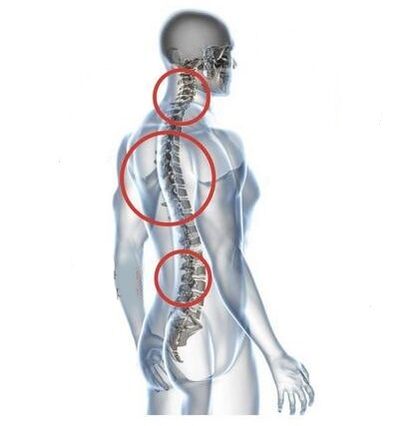

A medida que los discos intervertebrales y las vértebras se deforman, la condición del paciente empeora. El curso de la osteocondrosis se complica por síntomas neurogénicos causados por la compresión por osteofitos o la protrusión herniaria de las raíces espinales y la arteria vertebral. Aparecen dolores de cabeza, mareos, cambios en la presión arterial y disminuye la agudeza visual y auditiva.

Las indicaciones para la intervención quirúrgica incluyen la ineficacia del tratamiento conservador, así como las complicaciones de la osteocondrosis cervical, por ejemplo, mielopatía discogénica, síndrome de la arteria vertebral y síndrome radicular. Para descomprimir la médula espinal, los vasos sanguíneos y las raíces espinales se realizan las siguientes operaciones: